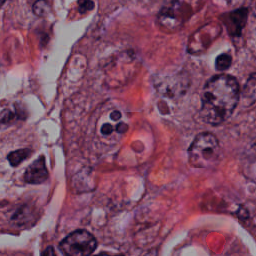

Blood Cell Artifact

Histopathology GMAIMMbench Cell Recognition

Blood Cell Artifact - L0 (Original)

L0 (Original)

Question

Which cell type is indicated in the highlighted area of the Histopathology image?

A epithelial cell B cytoplasm C dead cell D photoreceptor cell

Ground Truth: C. dead cell